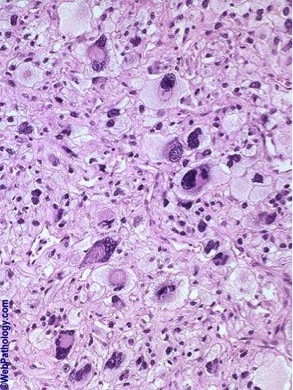

You discover a tumor in your pt which histologically shows typical spindle cells arranged in a “storiform” pattern. There are also bizarre giant cels shown below. Dx?

Malignant fibrous histiocytoma